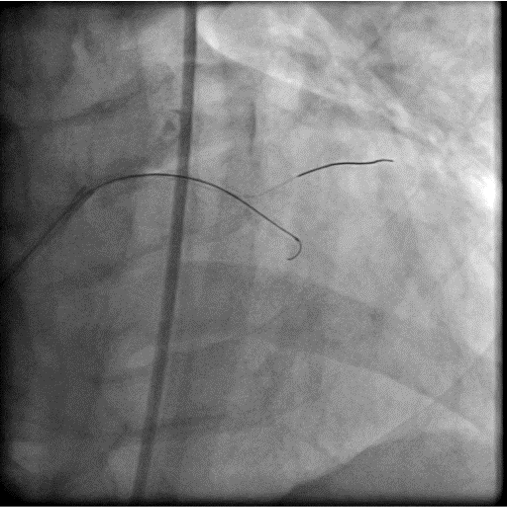

The coronary angiogram showed middle LAD CTO, LCX critical stenosis and RCA CTO with collateral from LCX. J-CTO score for LAD was 3 points . J-CTO score for RCA was 4 points. The CHIP PCI score was 11.

The procedure was done in two stage. For first stage, we use upfront IABP as a mechanical support with ECMO access route prepared and ECMO team standby. The LAD CTO was the first target as it was relatively short, not a donor vessels and would provide greatest benefit to the patient. With antegrade approach and wire escalation technique ( Fielder XTA, Fielder XTR, Gaia 1st), we finally punctured into the proximal cap with Gaia 3rd and immediately deescalate the wire to Sion black to navigate through the CTO body and finally managed to reach distal true lumen with a Sion Black. Then we did the circumflex lesion starting with a Sion Black. However, the Sion Black and Fielder XTR could not cross the lesion. We then escalate the wire to Gaia 1st.